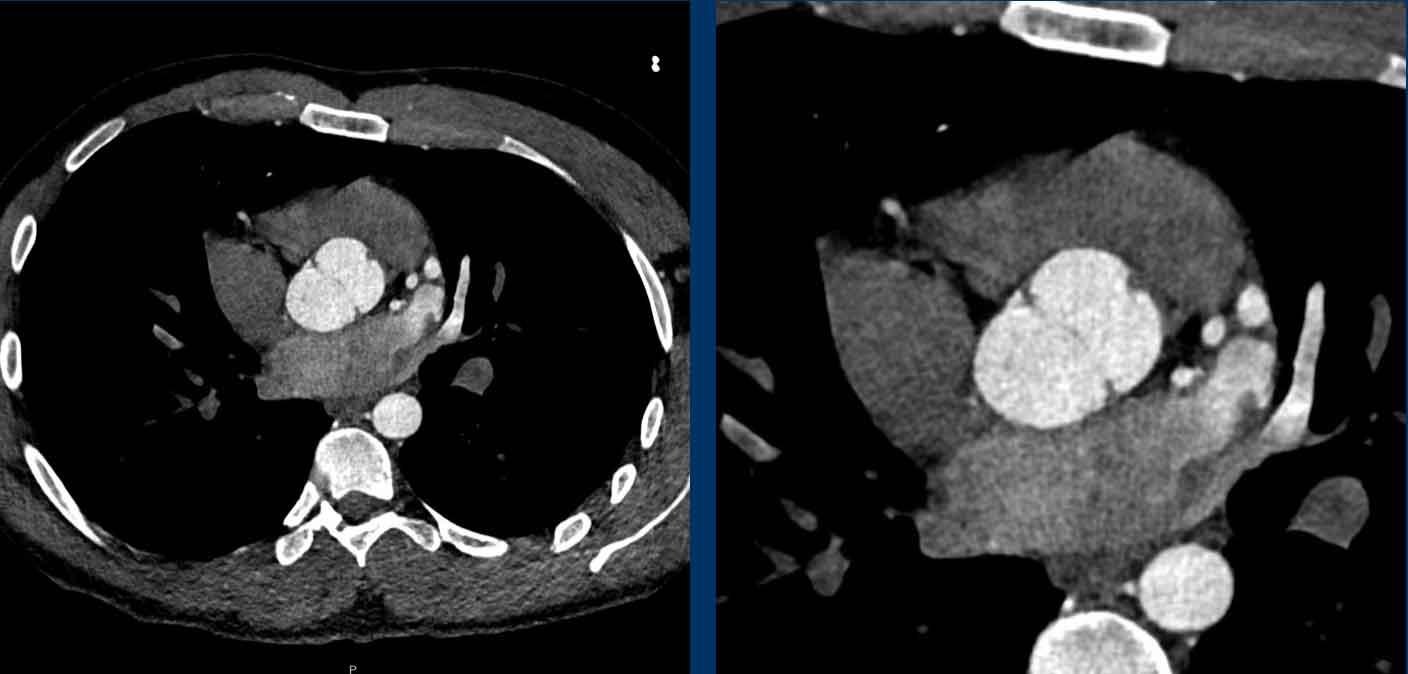

Huyết Khối

Khối trong tim thường gặp nhất là huyết khối, thường khu trú tại tiểu nhĩ trái (LAA), chủ yếu ở bệnh nhân rung nhĩ có giãn nhĩ trái đáng kể.

Tuy nhiên, huyết khối cũng có thể xuất hiện ở nhĩ phải liên quan đến catheter tĩnh mạch trung tâm, hoặc trong phình mỏm thất trái sau nhồi máu cơ tim cũ.

Cuộn qua các hình ảnh của bệnh nhân rung nhĩ.

Nhận xét các phát hiện?

Hình ảnh

Nhĩ trái giãn.

Có huyết khối trong tiểu nhĩ trái (mũi tên) lan rộng về phía nhĩ trái (đầu mũi tên).

Tại tiểu nhĩ trái, thường gặp khó khăn trong chẩn đoán phân biệt hình ảnh giữa huyết khối và hiện tượng ngấm thuốc không hoàn toàn do dòng chảy chậm, đặc biệt khi chụp ở thì thuốc sớm.

Vấn đề này có thể được giải quyết bằng cách chụp CT ở thì thuốc muộn hơn hoặc chụp ở tư thế nằm sấp.

Siêu âm tim qua thực quản được coi là tiêu chuẩn vàng.

Xảo ảnh dòng chảy chậm trong tiểu nhĩ trái, với hình ảnh ngấm thuốc không hoàn toàn của tiểu nhĩ trái ở thì sớm nhưng lấp đầy hoàn toàn ở thì thuốc muộn hơn.

U Nhầy (Myxoma)

U nhầy là một khối u lành tính tương đối hiếm gặp, nhưng là một trong những khối nguyên phát trong tim thường gặp nhất.

U thường xuất phát từ nhĩ, chủ yếu ở phía trái.

U thường có cuống và bám vào vách liên nhĩ.

U có tỷ trọng thấp không đồng nhất và có thể có vôi hóa.

Tùy thuộc vào kích thước, u có thể gây tắc nghẽn van tim, sa van và các biến cố thuyên tắc hệ thống.

U nhầy nhĩ trái phát hiện tình cờ.

Tim Ba Buồng Nhĩ (Cor Triatriatum)

Trong tim ba buồng nhĩ, nhĩ bị chia thành hai ngăn bởi một màng xơ cơ.

Màng này thường gặp hơn ở nhĩ trái.

Mức độ nặng của triệu chứng lâm sàng phụ thuộc vào kích thước lỗ thông trên màng.

Các trường hợp nhẹ hơn có thể không được phát hiện trong thời gian dài.

Tim ba buồng nhĩ trái (cor triatriatum sinistra) phát hiện tình cờ với hình ảnh ngấm thuốc muộn của ngăn phải nhĩ trái.

Trường hợp này ban đầu bị nhầm lẫn với huyết khối.

Tiếp tục xem hình ảnh MR…

Đây là hình ảnh MR của cùng trường hợp trên

Lấp đầy muộn của ngăn phải nhĩ trái trong tim ba buồng nhĩ trái (cor triatriatum sinistra).

Vách ngăn nhĩ trái mức độ nhẹ hơn trong tim ba buồng nhĩ, chỉ biểu hiện bằng một cấu trúc dạng dải mảnh, còn được gọi là ‘dải nhĩ trái’ (left atrial band)